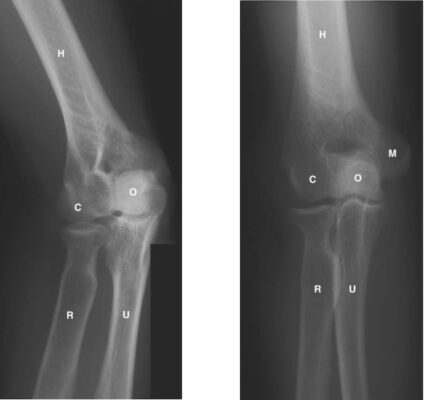

LIÊN HỆ X QUANG KHỚP KHUỶU

Ghi chú:

- H = Humerus; xương cánh tay

- O = Olecranon process of ulna; mỏm khuỷu xương trụ

- R = Radius; xương quay

- U = Ulna; xương trụ

- T = Trochlea of humerus; ròng rọc xương cánh tay

- M = Medial epicondyle of humerus; lồi cầu trong xương cánh tay

- C = Capitellum of humerus; chỏm con xương cánh tay